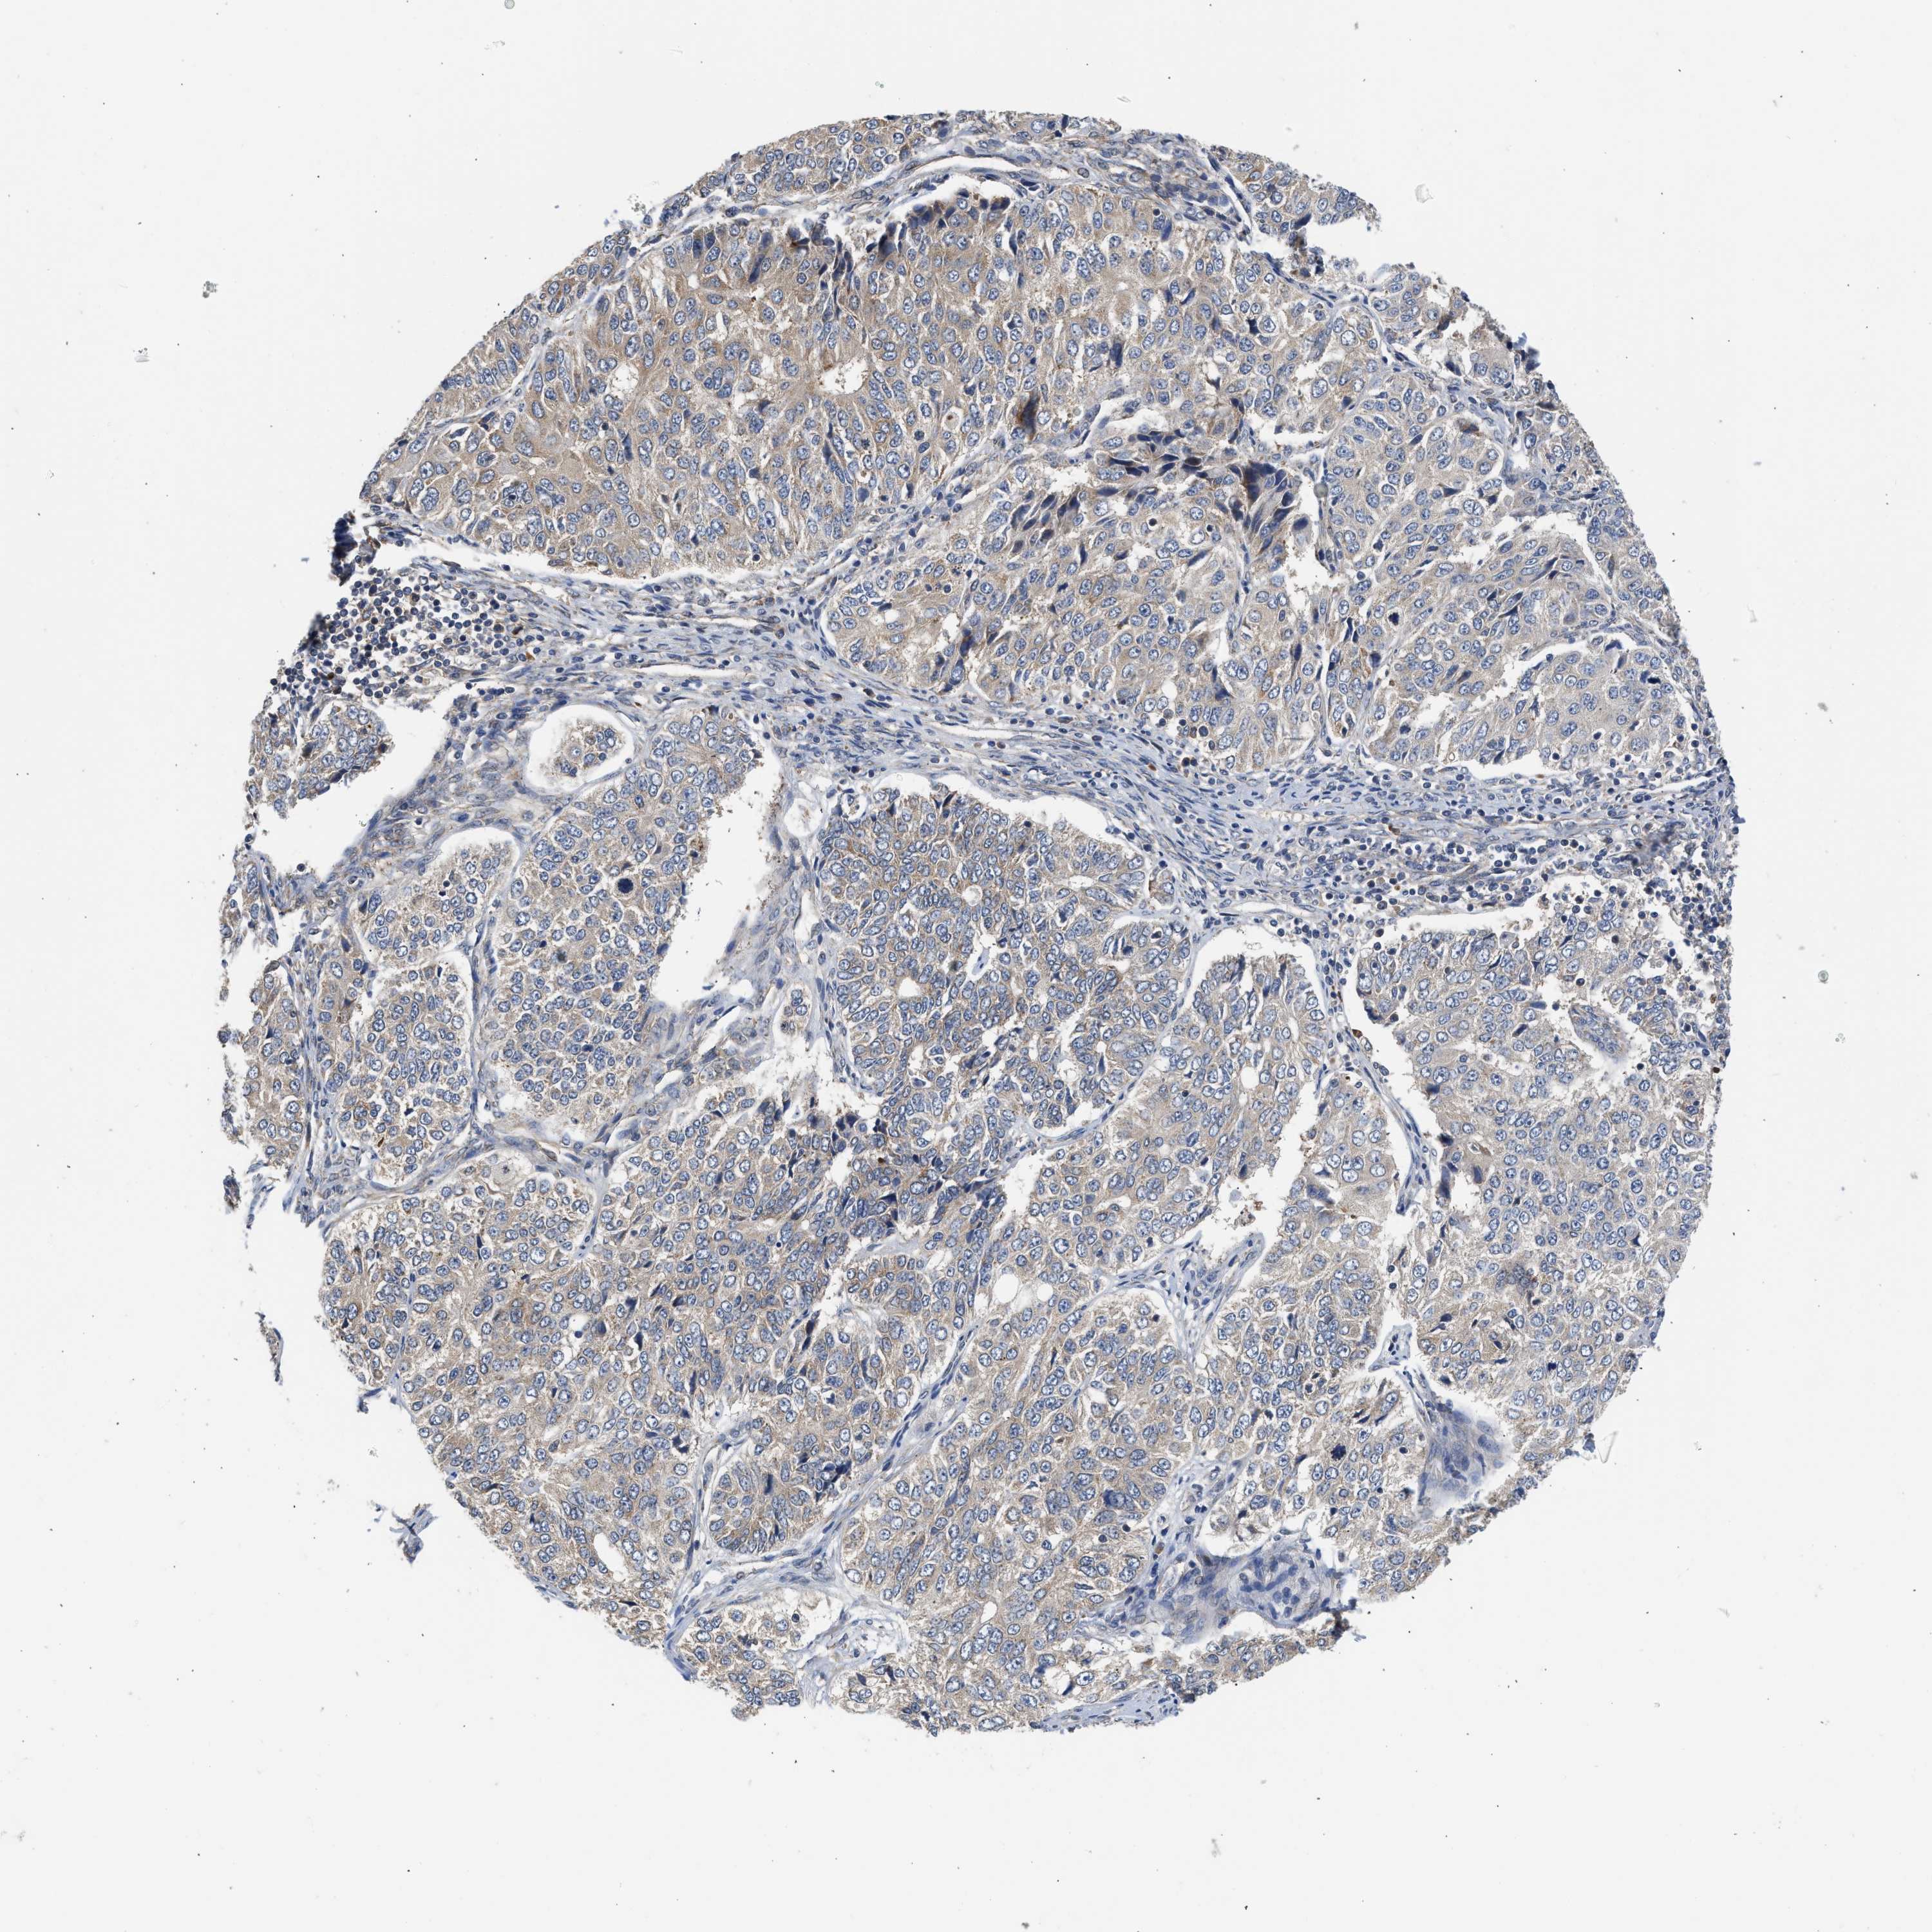

OVARIAN CANCER - Protein expressioni

A mouse-over function shows sample information and annotation data. Click on an image to view it in a full screen mode. Samples can be filtered based on level of antibody staining by selecting one or several of the following categories: high, medium, low and not detected. The assay and annotation is described here.

Note that samples used for immunohistochemistry by the Human Protein Atlas do not correspond to samples in the TCGA dataset.

Antibody stainingi

Antibody staining in the annotated cell types in the current human tissue is reported as not detected, low, medium, or high, based on conventional immunohistochemistry profiling in selected tissues. This score is based on the combination of the staining intensity and fraction of stained cells.

Each image is clickable and will lead to virtual microscopy that enables deeper exploration of all samples and also displays staining intensity scores, fraction scores and subcellular localization as well as patient and tissue information for each sample.